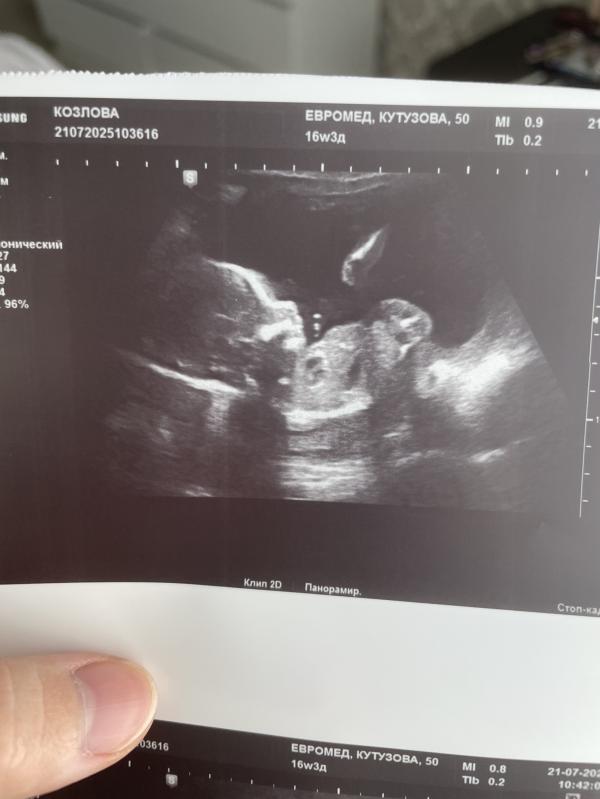

У меня такая же фотка с Евромед) мне кажется даже лица похожи, нам 32 недельки.